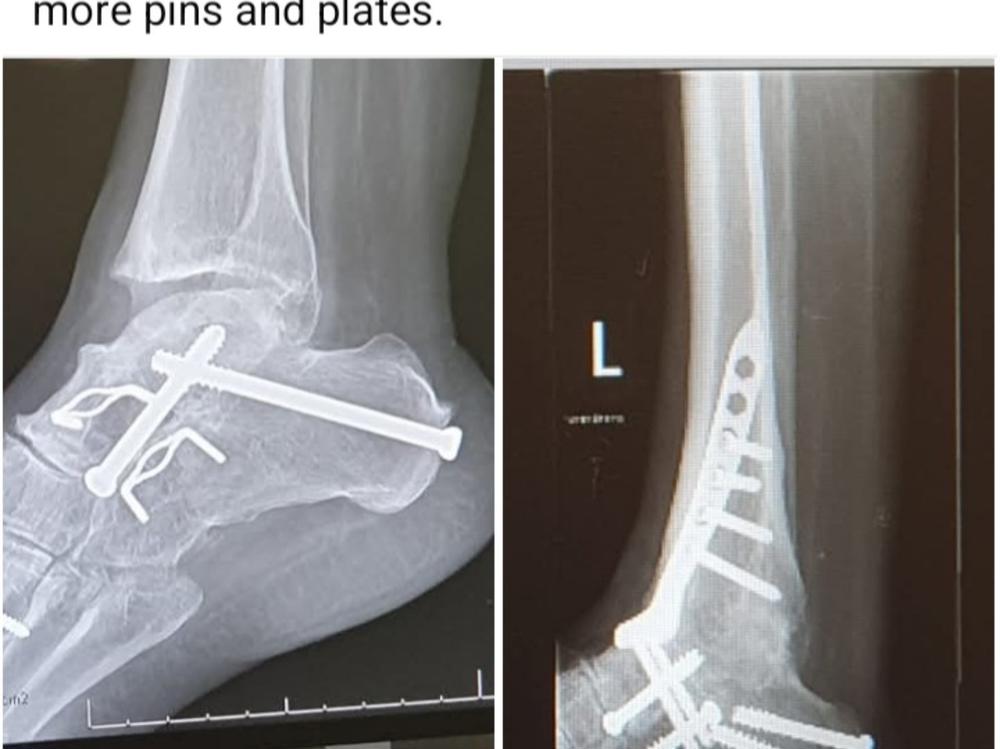

She lives in constant pain but somehow manages, most days, to put a smile on her face. She has had countless surgeries to fuse bones and due to the CMT has had multiple falls resulting in more surgeries - some which she is still waiting for due to ACC not accepting her claim. She gets tired doing simple things and getting out and about is really hard.